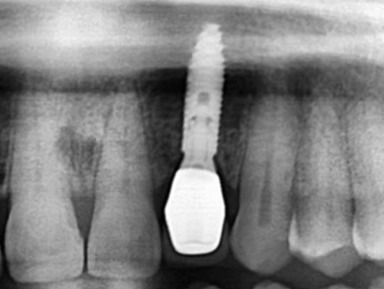

![]() |

| Phục hồi trên implant tại vùng thẩm mỹ như răng thật tại Nha Khoa Như Ngọc (21 Trần quang diệu, Hà Nội). |